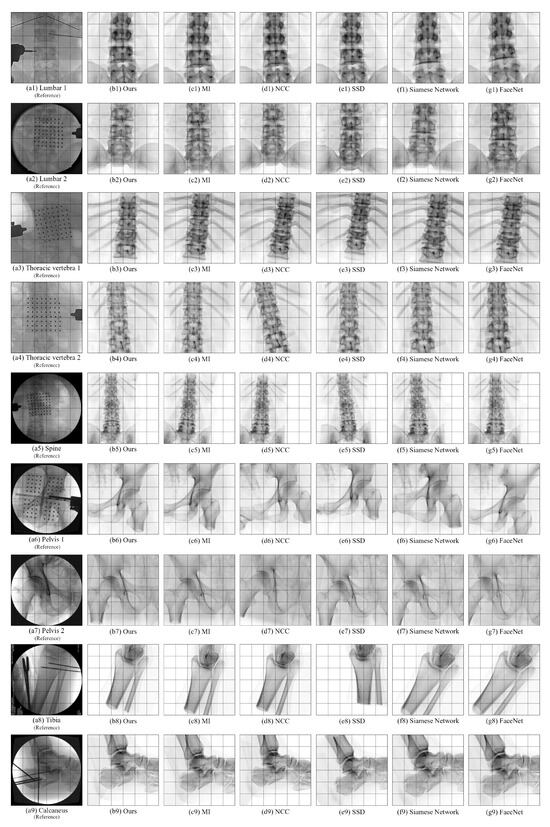

4.5. Comparative Experiments of Registration Algorithms

| Algorithm | Bone Type | Average Error of X Rotation / ° | Average Error of Y Rotation / ° | Average Error of Z Rotation / ° | Average Error of X Translation / mm | Average Error of Y Translation / mm | Average Error of Z Translation / mm | Average Registration Time / s |

|---|---|---|---|---|---|---|---|---|

| SSD | Lumbar 1 | 3.723 | 4.578 | 3.986 | 3.052 | 5.005 | 8.690 | 61.08 |

| Lumbar 2 | 3.690 | 2.468 | 2.726 | 2.267 | 16.194 | 8.639 | ||

| Lumbar 3 | 2.598 | 5.953 | 1.463 | 1.581 | 5.183 | 10.356 | ||

| Thoracic vertebra 1 | 13.035 | 8.614 | 3.915 | 8.009 | 1.223 | 8.464 | ||

| Thoracic vertebra 2 | 5.951 | 1.160 | 1.792 | 4.799 | 1.286 | 10.555 | ||

| Thoracic vertebra 3 | 5.142 | 1.712 | 3.950 | 5.484 | 8.544 | 15.533 | ||

| Thoracic vertebra 4 | 4.620 | 4.316 | 2.114 | 16.006 | 1.751 | 14.582 | ||

| Spine | 10.234 | 1.740 | 1.617 | 12.165 | 3.361 | 11.208 | ||

| Pelvis 1 | 11.077 | 5.547 | 2.511 | 3.837 | 2.663 | 6.221 | ||

| Pelvis 2 | 4.744 | 2.534 | 1.651 | 2.875 | 3.402 | 14.787 | ||

| Tibia | 4.550 | 9.989 | 9.410 | 10.999 | 4.369 | 5.166 | ||

| Calcaneus | 2.750 | 4.440 | 12.936 | 1.675 | 7.716 | 13.753 | ||

| NCC | Lumbar 1 | 3.258 | 1.683 | 0.737 | 2.212 | 7.603 | 4.182 | 61.80 |

| Lumbar 2 | 1.267 | 1.759 | 1.422 | 1.091 | 2.098 | 4.027 | ||

| Lumbar 3 | 3.898 | 1.172 | 0.560 | 2.163 | 7.645 | 5.649 | ||

| Thoracic vertebra 1 | 9.279 | 4.383 | 0.833 | 7.519 | 5.109 | 6.742 | ||

| Thoracic vertebra 2 | 6.402 | 4.854 | 4.558 | 2.816 | 6.941 | 4.325 | ||

| Thoracic vertebra 3 | 4.497 | 1.401 | 3.986 | 5.094 | 7.301 | 9.764 | ||

| Thoracic vertebra 4 | 9.643 | 1.157 | 1.281 | 9.412 | 0.184 | 7.363 | ||

| Spine | 7.598 | 0.115 | 1.024 | 8.685 | 9.761 | 11.525 | ||

| Pelvis 1 | 3.774 | 9.057 | 8.350 | 9.205 | 11.867 | 3.560 | ||

| Pelvis 2 | 8.481 | 4.837 | 6.500 | 8.868 | 3.868 | 4.276 | ||

| Tibia | 9.374 | 8.001 | 7.040 | 2.810 | 5.012 | 5.138 | ||

| Calcaneus | 0.207 | 6.988 | 2.897 | 2.899 | 1.881 | 15.986 | ||

| MI | Lumbar 1 | 5.976 | 2.148 | 2.408 | 1.310 | 7.922 | 5.484 | 59.41 |

| Lumbar 2 | 7.576 | 1.030 | 0.467 | 0.854 | 9.813 | 3.748 | ||

| Lumbar 3 | 4.917 | 4.354 | 0.276 | 3.746 | 6.800 | 3.947 | ||

| Thoracic vertebra 1 | 6.506 | 2.365 | 1.077 | 8.694 | 1.595 | 3.794 | ||

| Thoracic vertebra 2 | 1.422 | 0.936 | 3.358 | 3.156 | 2.775 | 6.203 | ||

| Thoracic vertebra 3 | 7.899 | 3.544 | 1.844 | 0.714 | 4.794 | 8.123 | ||

| Thoracic vertebra 4 | 6.546 | 2.873 | 6.148 | 0.469 | 2.295 | 5.637 | ||

| Spine | 5.510 | 0.364 | 3.185 | 8.540 | 4.761 | 2.559 | ||

| Pelvis 1 | 2.762 | 1.364 | 1.973 | 9.802 | 0.840 | 5.788 | ||

| Pelvis 2 | 3.879 | 3.054 | 1.795 | 5.028 | 1.882 | 7.962 | ||

| Tibia | 7.399 | 6.420 | 3.047 | 1.071 | 8.159 | 5.883 | ||

| Calcaneus | 5.769 | 6.759 | 4.747 | 1.359 | 4.488 | 7.308 | ||

| Siamese Network [17] | Lumbar 1 | 12.321 | 1.156 | 2.452 | 2.390 | 4.013 | 9.817 | 85.90 |

| Lumbar 2 | 10.792 | 3.091 | 0.907 | 3.632 | 6.290 | 8.256 | ||

| Lumbar 3 | 5.071 | 1.233 | 1.721 | 7.114 | 5.561 | 9.095 | ||

| Thoracic vertebra 1 | 4.698 | 4.640 | 1.096 | 6.680 | 3.713 | 14.319 | ||

| Thoracic vertebra 2 | 8.912 | 4.417 | 2.791 | 1.086 | 2.338 | 11.113 | ||

| Thoracic vertebra 3 | 2.169 | 1.273 | 3.541 | 1.478 | 6.854 | 12.723 | ||

| Thoracic vertebra 4 | 7.006 | 2.799 | 1.371 | 4.092 | 2.346 | 13.122 | ||

| Spine | 6.778 | 3.513 | 1.049 | 6.110 | 4.078 | 7.576 | ||

| Pelvis 1 | 10.407 | 3.111 | 5.189 | 4.311 | 5.125 | 6.297 | ||

| Pelvis 2 | 4.598 | 2.691 | 1.745 | 8.870 | 6.588 | 5.394 | ||

| Tibia | 7.967 | 9.225 | 3.046 | 0.104 | 10.223 | 11.749 | ||

| Calcaneus | 3.519 | 6.179 | 9.991 | 2.709 | 2.361 | 13.900 | ||

| FaceNet [19] | Lumbar 1 | 10.492 | 1.529 | 2.118 | 1.048 | 2.653 | 6.935 | 83.97 |

| Lumbar 2 | 12.086 | 2.478 | 1.754 | 1.487 | 8.517 | 14.821 | ||

| Lumbar 3 | 11.723 | 5.121 | 1.790 | 5.137 | 6.051 | 8.622 | ||

| Thoracic vertebra 1 | 6.208 | 2.650 | 1.207 | 3.987 | 7.017 | 11.059 | ||

| Thoracic vertebra 2 | 13.220 | 3.072 | 1.253 | 2.421 | 1.769 | 10.890 | ||

| Thoracic vertebra 3 | 9.350 | 2.131 | 6.797 | 0.339 | 10.311 | 12.198 | ||

| Thoracic vertebra 4 | 8.563 | 4.131 | 3.147 | 8.157 | 3.768 | 8.893 | ||

| Spine | 9.116 | 2.266 | 1.576 | 10.652 | 7.985 | 7.920 | ||

| Pelvis 1 | 4.897 | 3.762 | 8.898 | 9.023 | 9.158 | 9.114 | ||

| Pelvis 2 | 9.766 | 2.048 | 4.638 | 8.412 | 3.551 | 4.645 | ||

| Tibia | 4.457 | 6.847 | 11.349 | 1.032 | 8.848 | 15.491 | ||

| Calcaneus | 1.551 | 5.217 | 9.441 | 2.222 | 5.412 | 10.160 | ||

| Ours | Lumbar 1 | 0.916 | 0.465 | 0.304 | 0.182 | 0.248 | 1.400 | 61.38 |

| Lumbar 2 | 0.750 | 0.353 | 1.812 | 0.132 | 0.712 | 0.438 | ||

| Lumbar 3 | 0.492 | 1.171 | 0.657 | 0.065 | 0.670 | 0.577 | ||

| Thoracic vertebra 1 | 0.120 | 0.336 | 0.240 | 0.677 | 0.223 | 0.489 | ||

| Thoracic vertebra 2 | 0.212 | 0.555 | 0.834 | 0.348 | 0.639 | 0.375 | ||

| Thoracic vertebra 3 | 0.912 | 0.884 | 0.796 | 1.003 | 0.664 | 0.633 | ||

| Thoracic vertebra 4 | 0.986 | 0.425 | 0.765 | 1.036 | 1.674 | 0.401 | ||

| Spine | 0.727 | 0.271 | 0.414 | 0.277 | 0.730 | 0.837 | ||

| Pelvis 1 | 0.614 | 0.545 | 0.143 | 0.674 | 0.723 | 0.520 | ||

| Pelvis 2 | 0.914 | 0.832 | 0.416 | 0.266 | 0.215 | 0.297 | ||

| Tibia | 0.628 | 0.956 | 0.883 | 0.355 | 0.359 | 0.496 | ||

| Calcaneus | 0.294 | 0.158 | 0.904 | 0.331 | 0.753 | 0.217 |